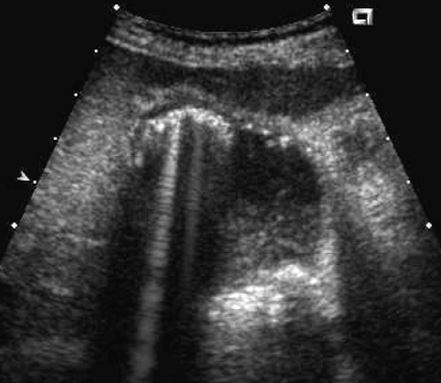

The gray-scale view shows a complex fluid

collection arising from the right kidney. In addition,

there is a simple-appearing, round, cystic structure

within the otherwise complex collection. The

power Doppler view shows flow in the apparent

cyst. All of these findings are consistent with a

pseudoaneurysm and adjacent hematoma.

Always put color Doppler on a “simple-appearing” cyst to make suer it is not something else!!!